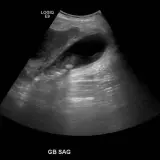

Over 2,100 interactive radiology cases, curated by radiologists for your level of training. Scroll, window, and view cases full screen — just like on PACS. Click linked findings in each writeup to jump straight to them on the image. Cases include sample reports, a focused discussion section, original illustrations, and videos.

PACSで期待されるツールを完備した完全インタラクティブな症例 — スクロール、ウィンドウ調整、ズーム、パン、計測、ROI、フルスクリーンモード。

重要な所見を症例画像上に直接ハイライトする豊富なアノテーション。症例解説内のリンクされた所見をクリックすると、スキャン上の正確な位置へジャンプできます。